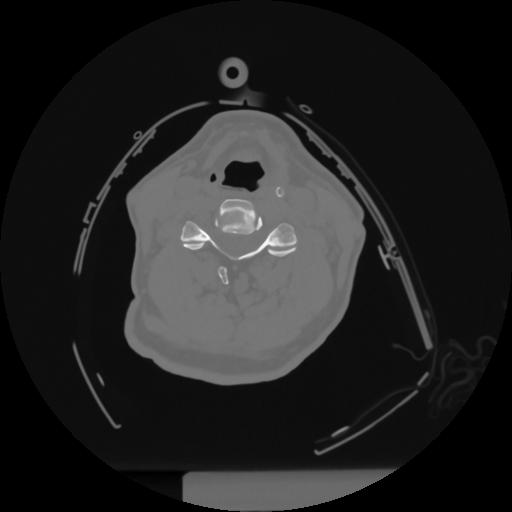

12 P.BLANDAS,,Vol,0.5,P.BLANDAS,,